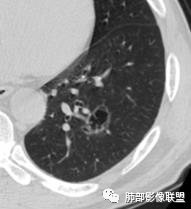

2.左肺下叶外基底段囊腔样病灶,轮廓柔和,壁厚薄不均,见壁结节。内见分隔或脊状突起。腔内见血管穿行。

3.囊壁外环以磨玻璃影,边界较清楚。

1.囊腔壁厚薄不均,壁结节,内有分隔,其内有血管穿行,指向新生物。

2.临近有边界清楚磨玻璃影,指向腺癌。